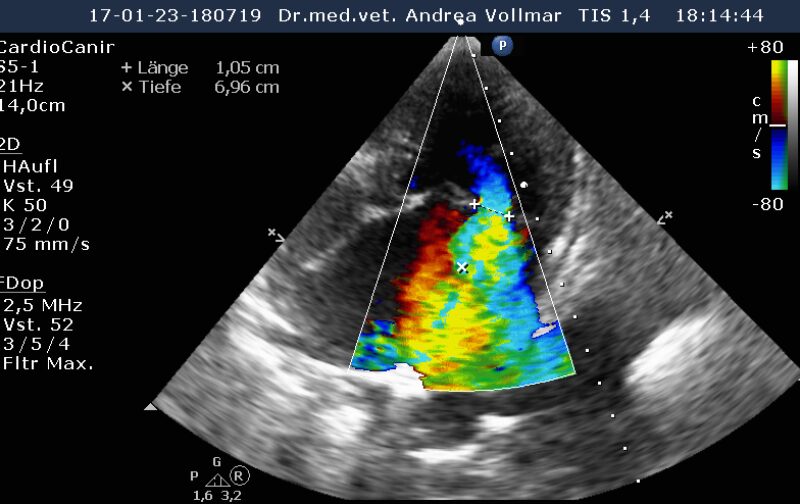

Degenerative Mitralklappeninsuffizienz (MI)

Die degenerative Mitralklappeninsuffizienz (MI) stellt beim Hund die Hauptursache für ein kongestives Herzversagen und kardial bedingten Tod dar. Im Krankheitsverlauf vergrößert sich mit zunehmender Schwere der Klappeninsuffizienz zunehmend der linke Vorhof und das diastolische Ventrikelvolumen nimmt zu, während das systolische Ventrikelvolumen erst mit nachlassender Kontraktilität bei Entwicklung einer Volumenüberlastungskardiomyopathie zunimmt. Bei kleineren Hunden unter 15 kg Körpergewicht ist dies oft erst später im Krankheitsverlauf der Fall, bei größeren Hunden über 15 kg hingegen häufig früher.

Am sichersten kann die Größe der einzelnen Herzabteilungen und der Schweregrad einer AV-Klappeninsuffizienz mit Hilfe der Echokardiografie beurteilt werden. Die Messung der Vorhofgröße vorzugsweise im 2D-Bild korreliert zuverlässig mit dem Ausmaß der MI. Mittels verschiedener Doppler- und Farbdoppler-Analysemethoden kann die Größe der Lücke in der Mitralklappe bestimmt und das regurgitierte Blutvolumen ermittelt werden.

Liegt eine Trikuspidalklappeninsuffizienz vor, bestimmt man anhand der Geschwindigkeit des Regurgitationsjets den arteriellen Lungendruck. Eine pulmonale arterielle Hypertonie (PAH) kann sich primär (idiopathisch) oder sekundär als Folge chronischer Lungen- oder Herz- und Gefäßerkrankungen entwickeln und beeinträchtigt Lebensqualität, Belastbarkeit und Lebenserwartung. Entsteht als Folge des Lungenhochdrucks eine Rechtsherzinsuffizienz, verschlechtert dies zusätzlich die Prognose.